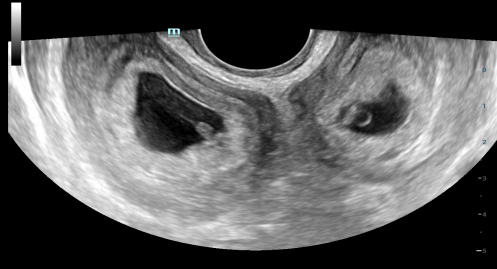

孕5周+6天🔼

孕21周🔼